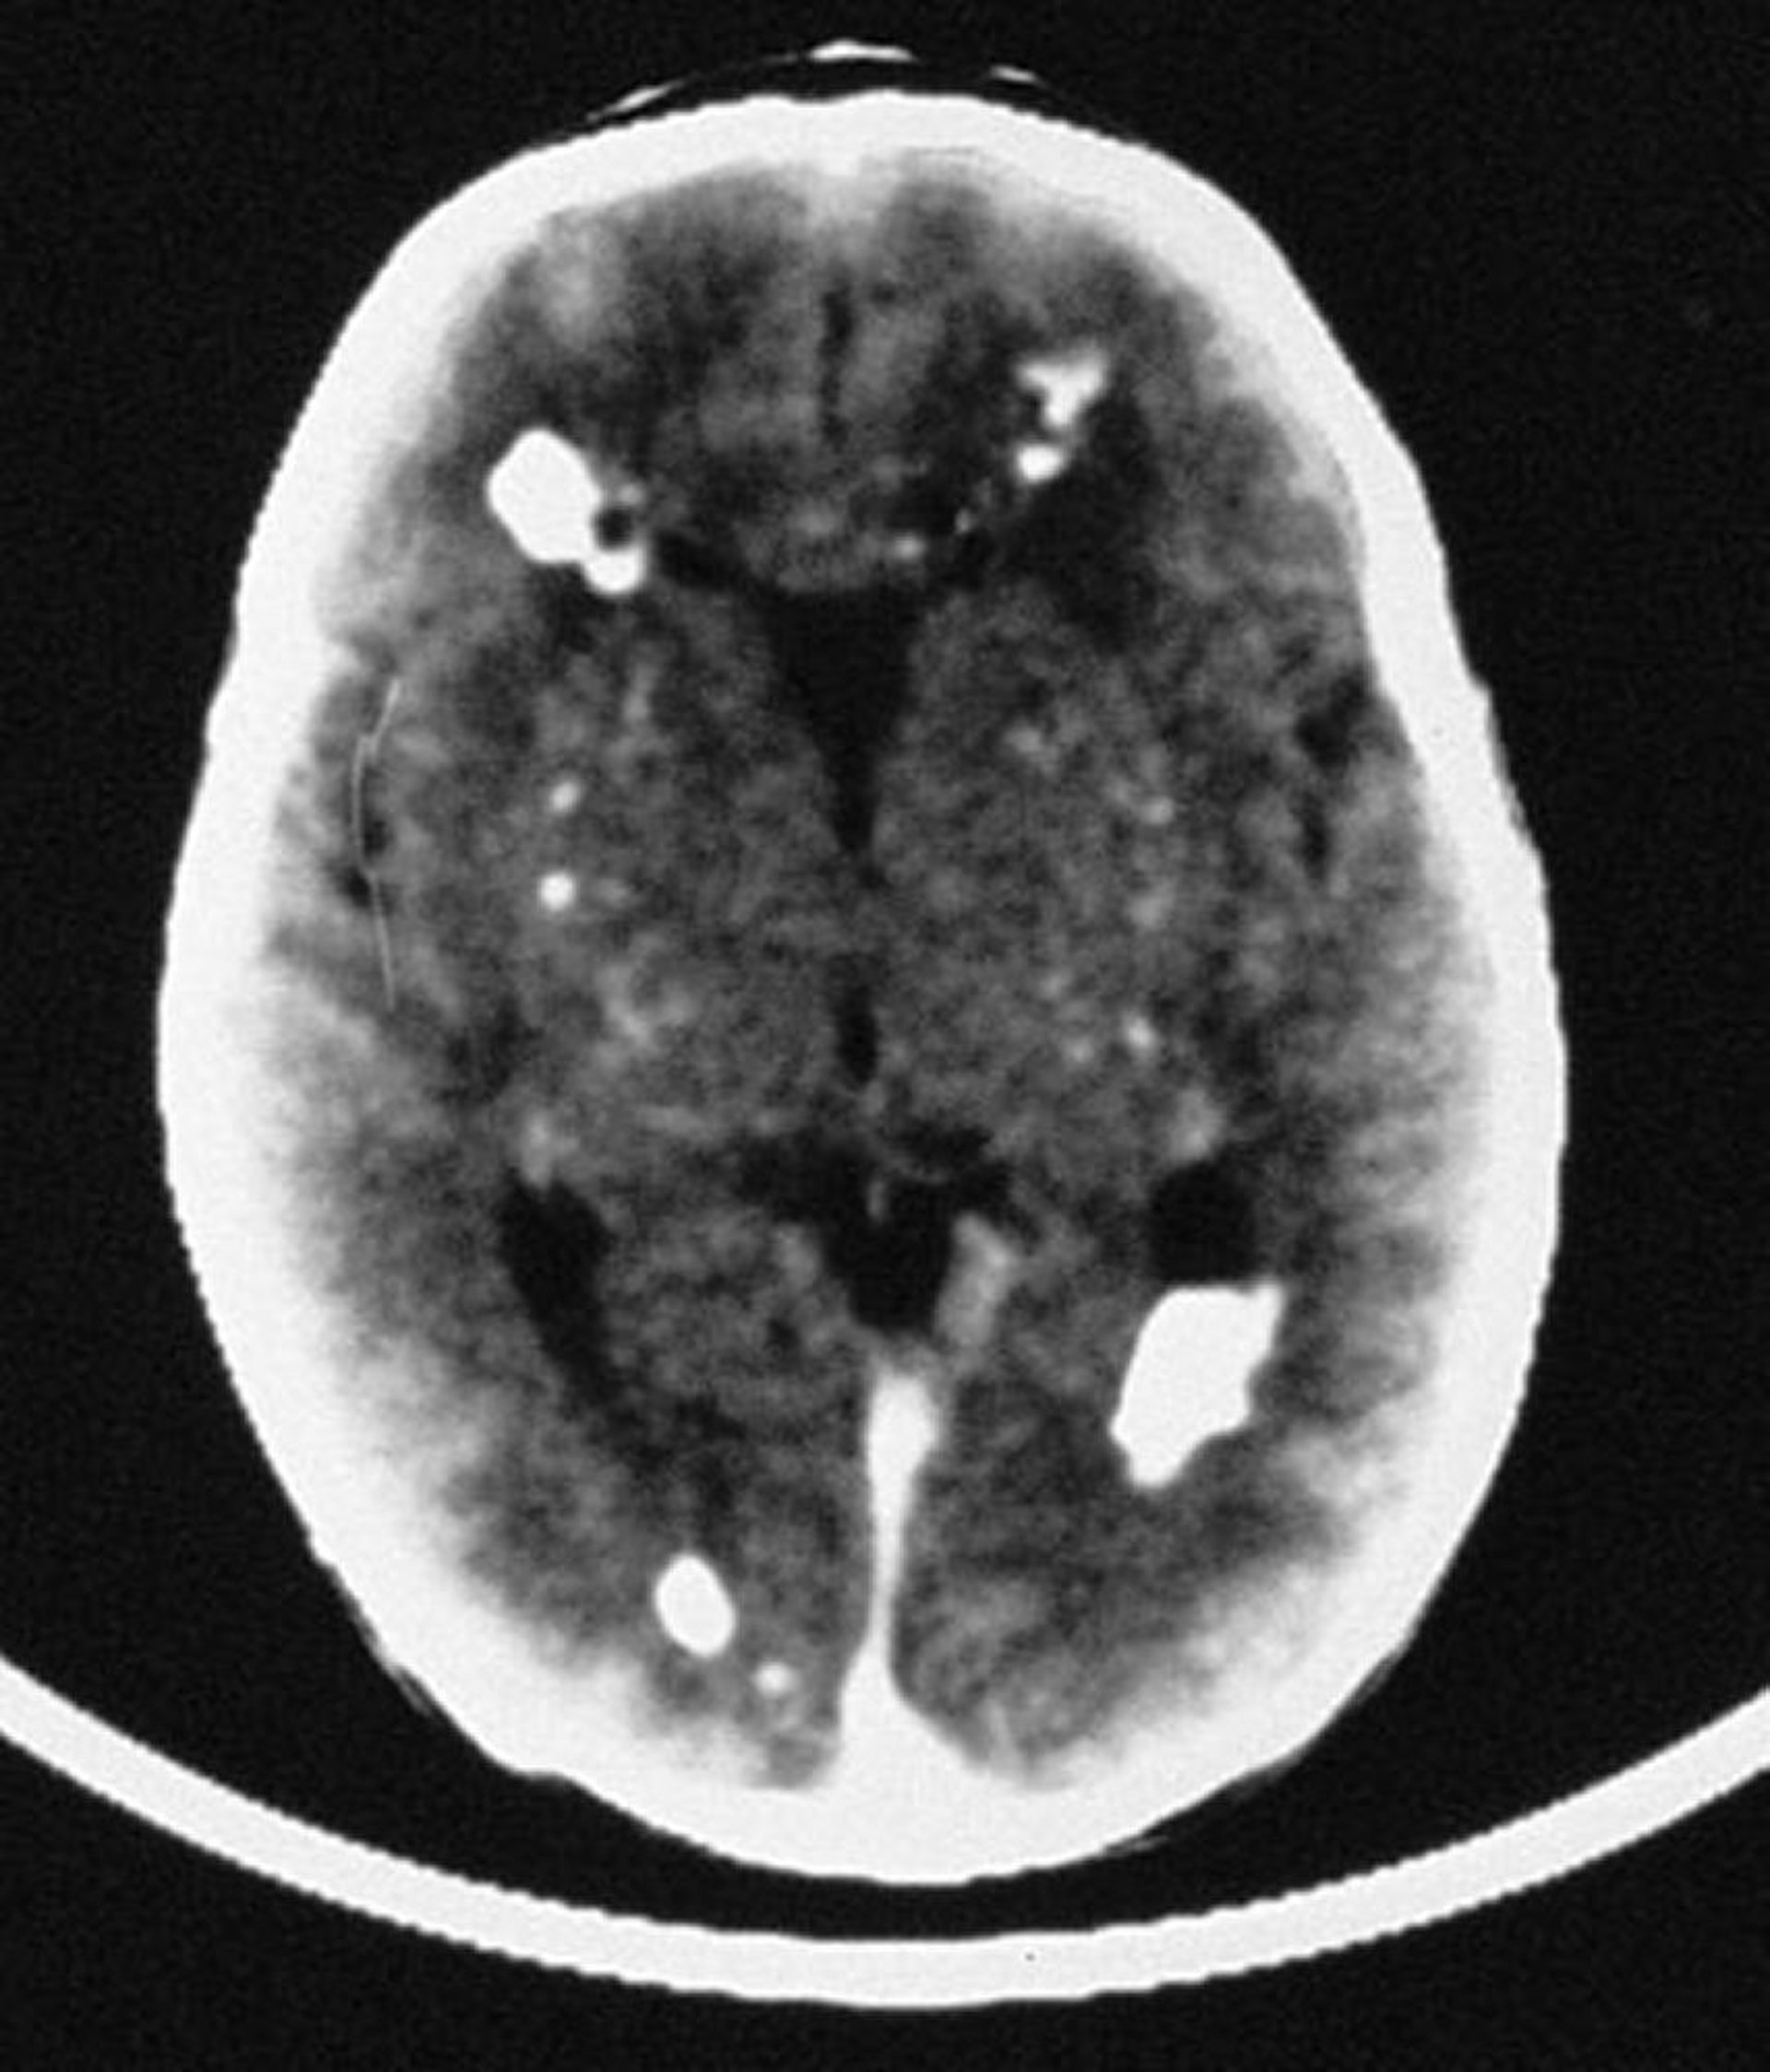

In this image, the CT scan reveals multiple intracranial calcifications, mostly periventricular in distribution, but also involving vascular structures of the brain.

By permission of the publisher. From Demmler G: Congenital and perinatal infections. In Atlas of Infectious Diseases: Pediatric Infectious Diseases. Edited by CM Wilfert. Philadelphia, Current Medicine, 1998.